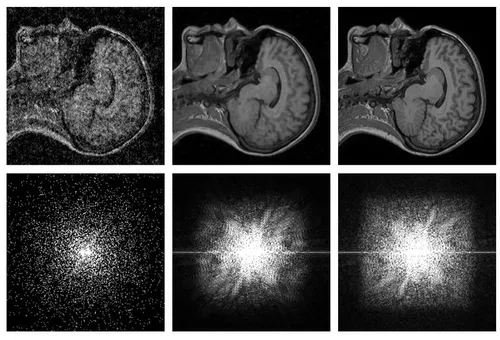

De foto's om de computer te trainen bestonden uit echte foto's, maar ook MRI scans. De foto's die verhelderd zijn door de AI, kwamen erg in de buurt van de zuivere foto. De computer had slechts een aantal miliseconden nodig om de foto aan te passen.

Het meest interessante aan dit onderzoek is dat er met twee korrelige foto's ook een zuivere foto gemaakt kan worden, zónder een zuivere foto nodig te hebben. Dit betekent niet dat de computer details kan aanpassen die er niet zijn, maar wel dat het een onzuivere foto zuiverder kan maken.

De toepassing kan gebruikt worden om normale foto's minder korrelig te maken, maar het kan ook een bijdrage leveren op medisch gebied. MRI scans kunnen verduidelijkt worden door de scans minder korrelig te maken.